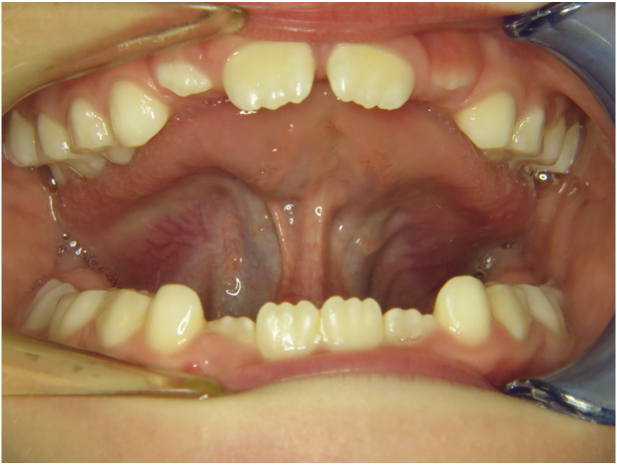

Wir sagten es bereits an anderer Stelle – Bilder sagen mehr als 1000 Worte…

Die Galerie zeigt verschiedene Problemstellungen unserer Patienten von Anfang bis Ende:

mykie® macht’s möglich – sehen Sie selbst: